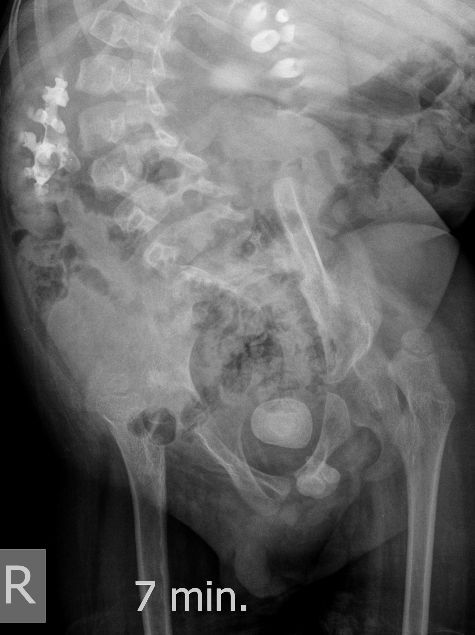

Поскольку откликов нет, добавляю экскреторные урограммы этого же пациента

DX0001.jpg

DX0002.jpg

DX0003.jpg

DX0004.jpg

DX0005.jpg

Нейрогенный мочевой пузырь (?), МКБ, конкремент мочевого пузыря, двухсторонний мегауретер, конкремент правой почки.

Всё верно, только что вот это ?

И что законтрастировалось на экскреторных урограммах около мочевого пузыря?